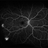

- sickle cell retinopathy, fluorescein leakage, fluorescein angiogram (FA), early phase, ultra-wide field imaging, ultra-widefield image, neovascularization (NV), right eye, proliferative retinopathy, non-perfusion

- Ultra-widefield fluorescein angiography of a 25-year old male with Proliferative Sickle Cell Retinopathy affecting his right eye. Patient stated that he was born with Sickle disease (SC), and has yearly eye exams. He noted no vision concerns over the last year but has typically experienced sickle attacks about 1-2 per year. The physician noted that the fluorescein obtained showed peripheral nonperfusion affecting the patient's nasal and temporal retina as well as neovascularization affecting his left eye more than his right. He recommended pan retinal photocoagulation in his left eye for his temporal and nasal retina, as as well as his right eye following.